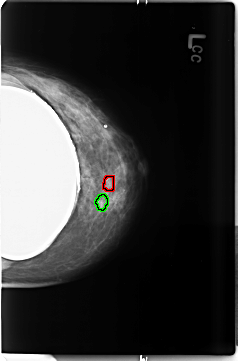

B_3497_1.LEFT_MLO

LEFT_MLO LINES 4624 PIXELS_PER_LINE 3080 BITS_PER_PIXEL 12 RESOLUTION 50 OVERLAY

FILE: B_3497_1.LEFT_MLO.OVERLAY

TOTAL_ABNORMALITIES 2

ABNORMALITY 1

LESION_TYPE CALCIFICATION TYPE PUNCTATE-PLEOMORPHIC DISTRIBUTION CLUSTERED

ASSESSMENT 4

SUBTLETY 3

PATHOLOGY MALIGNANT

ABNORMALITY 2